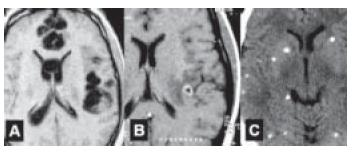

Homem de 38 anos de idade procurou unidade de emergência com déficit motor e sensitivo no membro superior direito, com evolução de alguns dias. Não apresentava náuseas ou vômitos, e sua pressão arterial medida foi de 140x90 mmHg. De antecedente fumava 20 cigarros/dia, mas nega etilismo. Tem antecedentes de uso de maconha, porém nunca usou drogas endovenosas. Ao exame, apresentava hemiparesia direita, sensitivo-motora, de predomínio braquio-facial, com hiperreflexia nos membros à direita. Além disso, foi observado o aparecimento de movimentos coreicos no dimídio direito. Fundoscopia foi normal. RNM com imagens ponderadas em T2 mostram lesão ovalada no núcleo subtalâmico esquerdo, com bordo hiperintenso e centro hipointenso (vide figura). RX tórax foi normal. Hemograma mostrou 2 800 leucócitos, com 300 linfócitos. HIV foi positivo, inclusive no Western blot. LCR lombar mostrou discreta pleocitose, linfomonocitária (14 células) com 52 mg/dL de proteínas e 88 mg/dL de glicose. Testes com látex foram negativos, bacterioscópico e micológico direto, negativos.

A doença demonstrada pelos exames de imagem é causada por